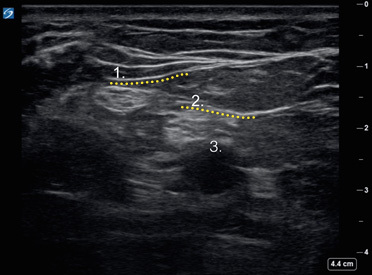

Popliteal Sciatic Nerve Bifurcation 1 Image

Common Peroneal Nerve

Tibial Nerve

Popliteal Artery